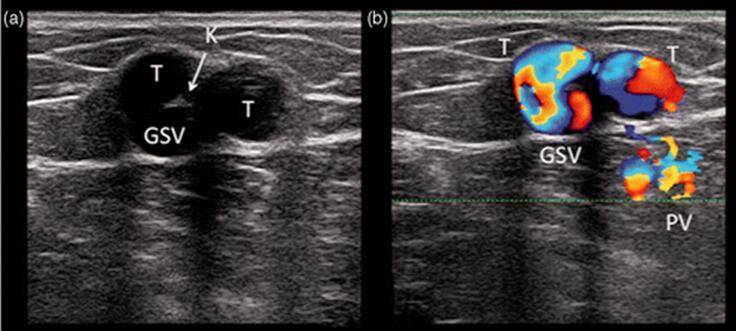

图15。复发的N2-N3返流点:(一)N2-N3返流点既往曾高位结扎但复发。以前的结扎的线结(K)可以通过超声彩色多普勒清晰的检测到,结合隐静脉主干(GSV)和复发的功能不全的属支(T)。(b)出现返流点的彩色多普勒证据,以及不能正常引流穿通支静脉(PV)的情况。